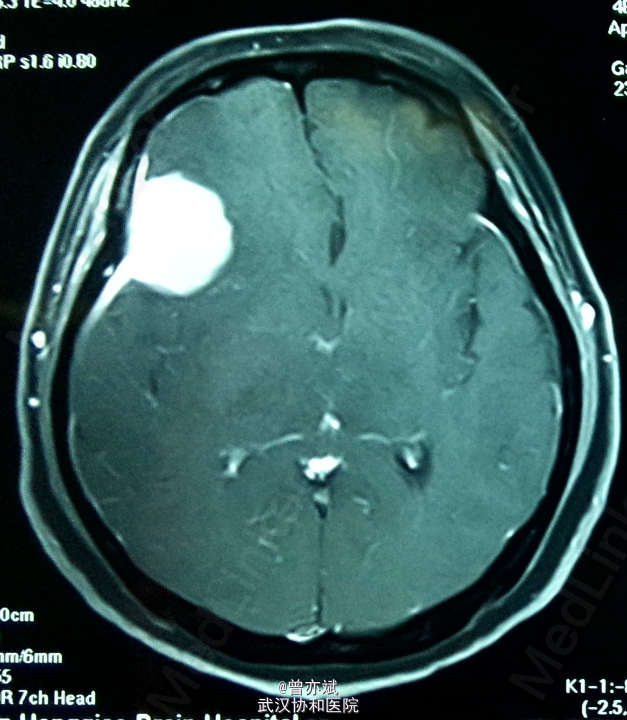

患者女,48岁,因“头晕1年”入院。近来出现左侧肢体肌力下降。

查体除左侧肢体肌力稍差4+,余无阳性体征。MRI如下

诊断:脑膜瘤 处理:手术切除。 病理报告为脑膜瘤。